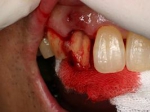

抜歯を行う。折れていた位置がかなり深い位置であるのがわかる。

歯根も抜歯